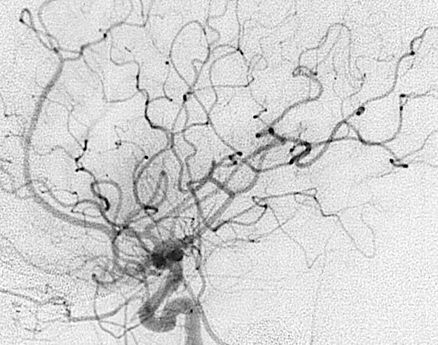

典型的には、若年者に頭蓋内出血あるいは症候性てんかんなどで発症する疾患です。未治療の状態では年間に約3%の確率で出血すると言われており、出血した場合神経症状を後遺したり最悪の場合生命に危険が及ぶこともあります。治療の目的は異常な血管網を閉塞させて、結果として出血を予防することです。閉塞までは少し時間がかかり、治療から3年後の閉塞率は奇形の大きさにもよりますが、60-90%程度です。完全な閉塞が確認されればほぼ出血の危険性はなくなりますが、少しでも残った場合は出血の危険性は残ります。もし病変が残存した場合は再度治療を行い閉塞に導くことも可能です。